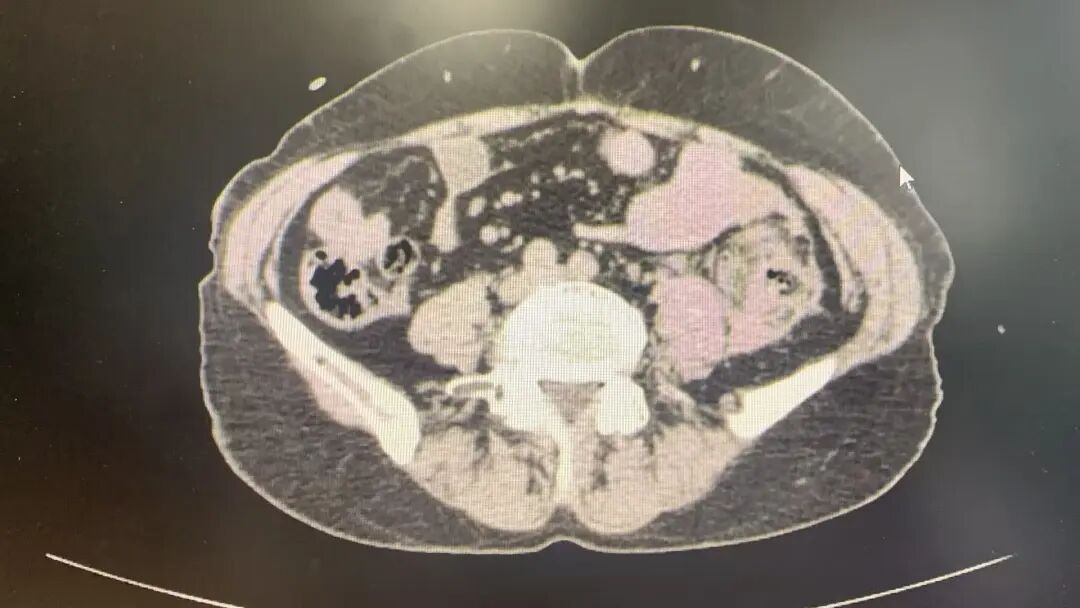

入院即启动绿色通道。腹部CT检查提示:降结肠周围脂肪间隙模糊,腹腔内可见积血。此时患者血压129/84mmHg,心率77次/分,结合体征,初步判断为肠系膜损伤伴活动性出血,邀请胃肠外科紧急会诊。

术中,见腹腔内积聚大量鲜红色血液及血凝块,但未见消化液泄漏。团队果断启用自体血回输技术,将出血收集、过滤、清洗、净化后安全回输,既争分夺秒又节约血源。在清除了约2500毫升的积血与血块后,真正的“破裂点”终于浮出水面:降结肠系膜血管破裂,周围组织严重毁损,一段约7厘米的降结肠呈“袖状”撕脱。血肿范围广泛,向内累及腰椎旁,向外达左肾外侧,上至胰腺下缘及脾脏,下抵盆腔,损伤范围之大,让手术难度陡增。